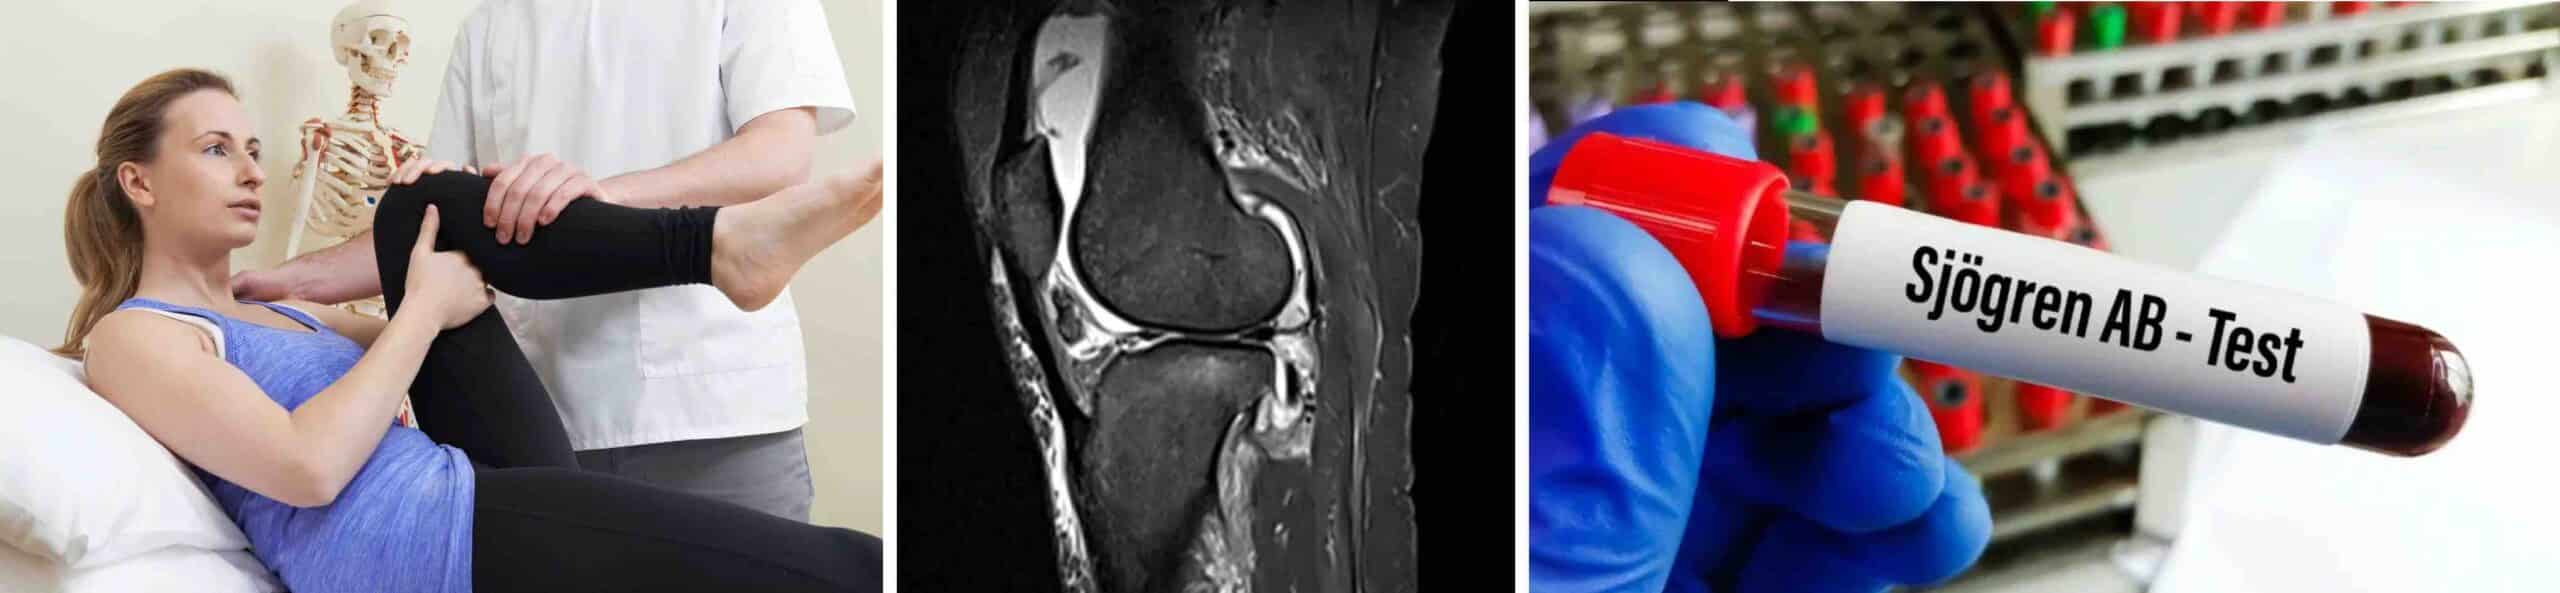

O diagnóstico da síndrome de Sjögren é feito pela história clínica detalhada, exame físico e exames complementares. Pacientes com sintomas da doença devem fazer uma série de exames, incluindo exames de sangue, exame oftalmológico e biópsia das glândulas salivares. A inflamação no joelho causada pela síndrome de Sjögren deve ser suspeitada nos pacientes com diagnóstico da doença que também se queixam de dor nos joelhos. A ressonância magnética é o principal exame para avaliação do joelho.

O tratamento da dor no joelho em pacientes com diagnóstico de síndrome de Sjögren envolve uma abordagem multidisciplinar. As opções mais prescritas pelos médicos especialistas são: anti-inflamatórios, imunossupressores, fisioterapia, mudanças no estilo de vida e cuidados com a alimentação. A doença ainda não tem cura conhecida, mas os tratamentos podem ajudar a diminuir os sintomas e melhorar a qualidade de vida do paciente.